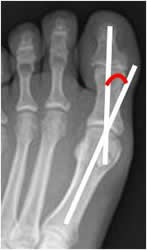

Angulo del hallux valgus:

Medido en Rx AP. Se traza entre los ejes longitudinales del 1º metatarsiano y la falange proximal del hallux. (1). El ángulo normal debe ser inferior a 15º. Valores superiores se considera hallux valgus. (2). (Fig 92 y 93).

Fig 92. Angulo de hallux valgus.

Rx AP. Angulo de hallux valgus normal.

Fig 93. Hallux valgus.

A y B: Rx AP. Incremento de los ángulos, por hallux valgus.